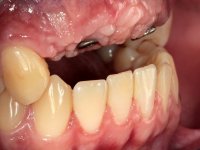

Paciente do sexo masculino, com 22 anos de idade e não fumador. Apresentou-se na consulta 6 meses após um acidente de viação em que perdeu os dentes 21, 22, 23 e 24. Os dentes 12 e 11 apresentavam mobilidade grau 3 apresentando-se também com extracção indicada. A arquitectura gengival da zona desdentada apresentava-se retraída e planificada.

O paciente foi observado conjuntamente e a dúvida que surgiu de imediato foi se seria possível com a regeneração óssea a efectuar poder ser reabilitada naturalmente a zona das papilas interdentárias. Nesse sentido foi feito um enceramento de diagnóstico que contemplaria as duas hipóteses, utilizando ou não a cerâmica gengival. A confecção desse enceramento foi fundamental para expor ao paciente a dificuldade da reabilitação. O wax-up deu origem a um mock-up que foi aprovado pelo paciente e que simultaneamente serviu de guia imagiológica. O caso foi planificado cirurgicamente e realizada uma guia cirúrgica com que foram colocados os implantes. Após 10 semanas foi feita a 1ª impressão para confecção da ponte provisória. Foram criados os primeiros perfis de emergência na gengiva artificial e foi digitalizado o modelo. Por processo de CAD-CAM foi confeccionada uma ponte provisória aparafusada baseada no enceramento de diagnóstico. A ponte trabalhou durante 8 semanas os tecidos moles que foram fielmente copiados numa impressão com técnica de moldeira aberta. Os transferes foram individualizados com resina composta para copiarem fielmente os perfis de emergência criados pela ponte provisória. Confeccionado o modelo de trabalho definitivo, foi realizada uma infra-estrutura em zircónio seguindo a orientação do enceramento de diagnóstico. O assentamento da infra-estrutura foi testado em boca e simultaneamente foi novamente impressionados os tecidos moles com um silicone fluido. Nessa consulta foi feito o levantamento da cor. Os dentes 13 e 23 apresentavam uma saturação anormalmente forte que resolvemos não valorizar, optando por privilegiar a relação com o sector antero-inferior. Foi realizada uma nova gengiva artificial com a impressão que acompanhou a impressão de arrasto com a infra-estrutura. Após a colocação da cerâmica na infra-estrutura foram coladas as meso-estruturas. O trabalho final foi aparafusado lentamente permitindo a adaptação dos tecidos moles.